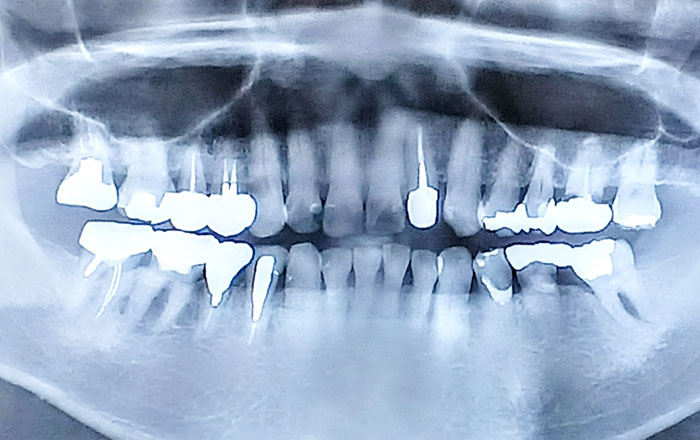

抜歯を提案されたときこそ、精密な診断が重要になります。

通常のレントゲンは平面的な画像であるため、歯根の形や周囲の骨の状態を十分に把握できないことがあります。一方、歯科用CTを使えば、顎の骨や歯根を三次元で確認でき、破折の有無や病巣の広がりまで、より正確に読み取ることが可能です。

抜歯は、CTなどの精密な検査をもとに、治療の選択肢とそれぞれのメリット・デメリットを理解したうえで判断するのが望ましいと言えるでしょう。場合によっては、他の歯科医院でセカンドオピニオンを受けるのもひとつの方法です。